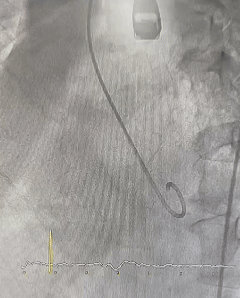

Imagem da semana

Lembram do desafio da semana passada? A imagem acima é o complemento e resposta para a nossa pergunta: fechamento percutâneo de CIV pós-IAM.

Fácil, né?!